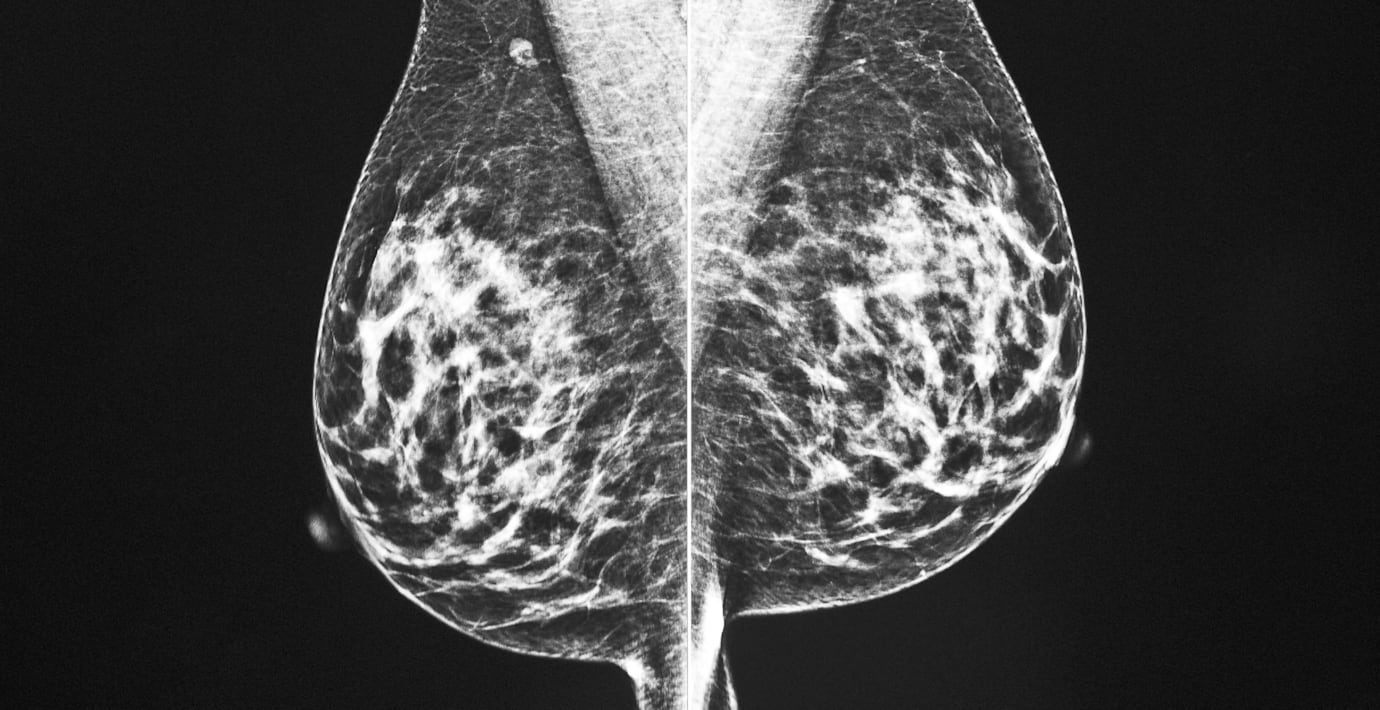

Arkivbild: Mammografi. (Eli Hartman / AP)

Bröstcancer är den oftast diagnosticerade cancerformen.